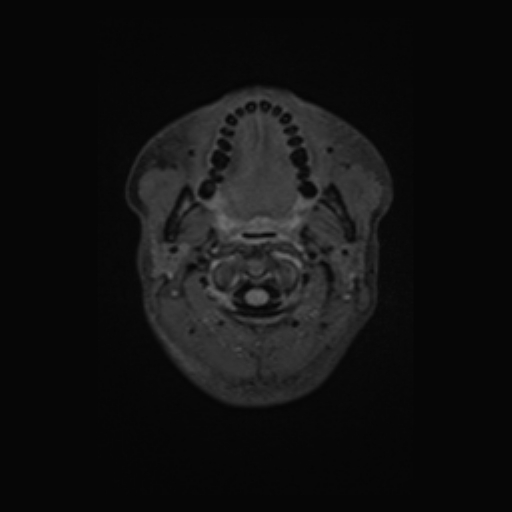

Nome Paziente: MACARI^NATALIA Identificativo: VSM_01222260 Data di Nascita: 07-06-1995 Sesso: F

Esame: RM ENCEFALO MDC del 24-03-2026